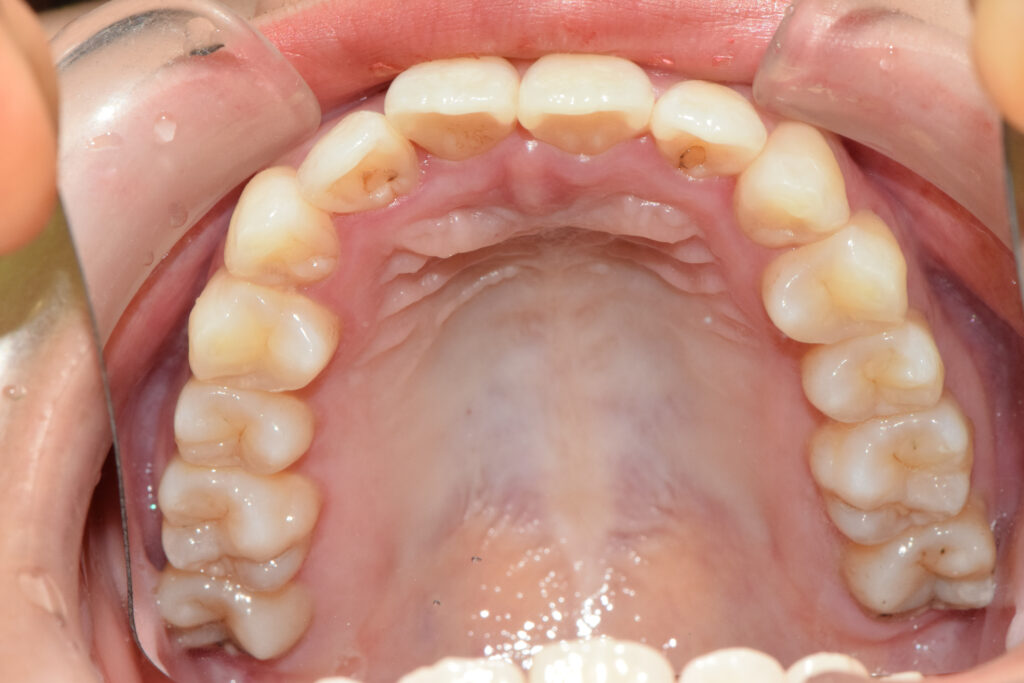

上顎

治療後